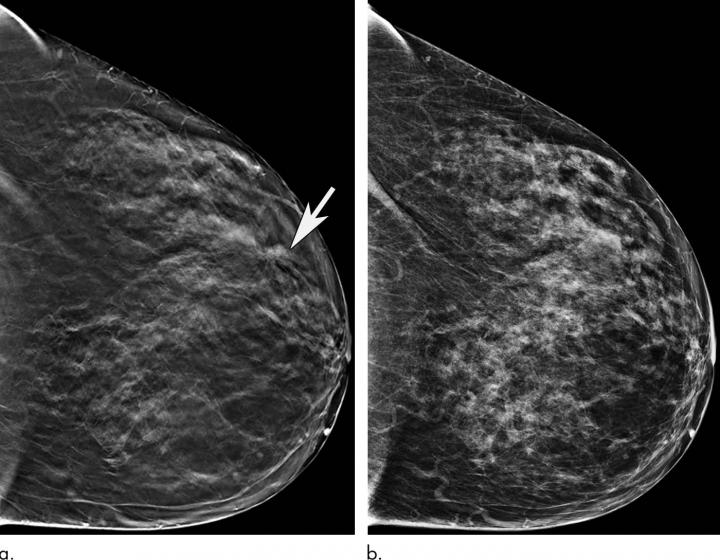

OAK BROOK, Ill. - Mammography remains an effective method for breast cancer screening in women ages 65 and older, with the addition of a 3-D technique called tomosynthesis improving screening performances even more, according to a study published in the journal Radiology .

Breast cancer is the most common cancer and the second most common cause of death from cancer among women in the United States. Research has shown that digital 2-D mammography (DM) is effective at reducing breast cancer-related mortality through early detection, when the cancer is most treatable. In 2011, the U.S. Food and Drug Administration approved tomosynthesis, also known as 3-D mammography, for breast cancer screening. Since then, it has become widely used as an adjunct to DM.

In the new study, researchers at Massachusetts General Hospital (MGH) sought to learn more about the performance of screening mammography in the older population and the added value of tomosynthesis. They compared screening mammograms from more than 15,000 women (mean age 72.7 years) who underwent DM with those of more than 20,000 women (mean age 72.1 years) who underwent tomosynthesis. Both approaches were highly effective at detecting cancer, but tomosynthesis had some advantages over the 2-D approach, including a reduction in false-positive examinations. Tomosynthesis also had a higher positive predictive value, the probability that women with a positive screening result will have breast cancer, and higher specificity, or the ability to distinguish cancer from benign findings, than DM.

"We've shown that screening mammography performs well in older women, with high cancer detection rates and low false-positives, and that tomosynthesis leads to even better performance than conventional 2-D mammography," said study lead author Manisha Bahl, M.D., M.P.H., radiologist at MGH and assistant professor of radiology at Harvard Medical School. "For example, the abnormal interpretation rate, which is the percentage of women who are called back for additional imaging after a screening mammogram, is lower with tomosynthesis than with conventional 2-D mammography. We also found that fewer cancers detected with tomosynthesis were lymph node-positive, suggesting that we are detecting cancers at an earlier stage. Detecting breast cancers at an early stage is the goal of screening mammography."